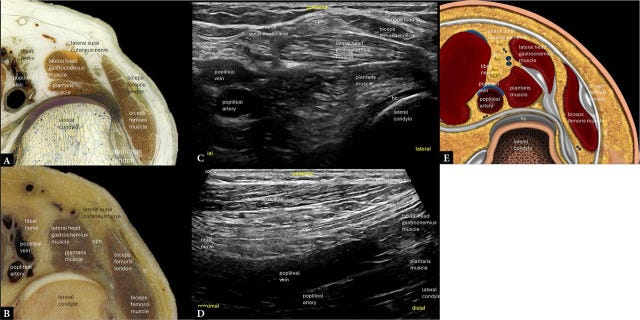

En la zona media, la atención se centra en la fosa poplítea. Con una vista transversal se identifican primero los cóndilos femorales, que sirven como referencia ósea, y luego el paquete neurovascular: nervio tibial en la superficie, seguido por la vena poplítea, y al fondo, la arteria, como si el cuerpo hubiera decidido proteger lo más vital con capas. Ajustando la frecuencia, se puede ver también la cápsula articular posterior y el ligamento cruzado posterior, este último apareciendo oblicuo, casi tímido, pero fundamental.

La región lateral presenta un reto mayor. La anatomía se vuelve más estratificada, más densa. En una vista longitudinal, se observa el músculo bíceps femoral en su parte proximal, y un poco más abajo, la cabeza lateral del gastrocnemio. El tendón del bíceps, que resulta de la unión de sus dos cabezas, desciende con firmeza hasta insertarse en la cabeza del peroné. En su trayecto se divide, casi como si dudara, para rodear el ligamento colateral lateral. De la cabeza corta del bíceps parte un fascículo anterior que se dirige hacia la meseta tibial, cerrando así un triángulo de referencias anatómicas útiles y constantes.

En los planos más profundos, el cuerno posterior del menisco lateral se presenta encajado entre el cóndilo femoral lateral y la tibia con la cabeza del peroné, como un libro cuidadosamente colocado entre dos sujetalibros. En esta zona, el nervio peroneo común también hace su entrada. Su trayecto, justo por detrás del tendón del bíceps femoral, lo lleva a dividirse en sus ramas: profunda, superficial y recurrente. Saber exactamente dónde está no es solo un ejercicio anatómico, es una necesidad clínica.